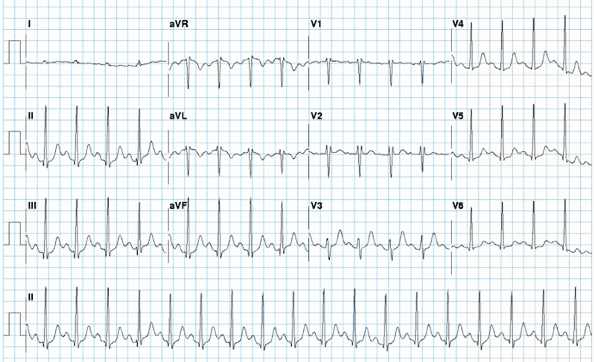

[Figure caption and citation for the preceding image starts]: Síndrome de Wolff-Parkinson-White (WPW) em um paciente com cardiomiopatia obstrutiva hipertróficaDo acervo do Dr. Mithilesh K. Das [Citation ends].